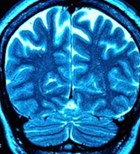

מהי פקקת ורידים עמוקה? כיצד נוצרת קרישיות יתר של הדם? כל...